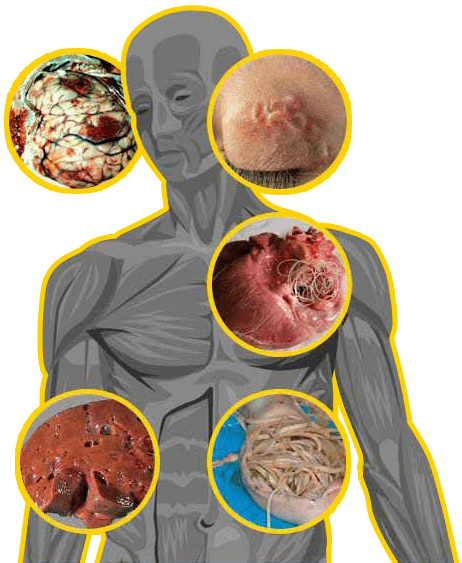

Parasites are multicellular protozoan organism, living at the expense of their host and make harm. Parasites first appear in intestines, then spread around the organism damaging all vital organs of a person:

Brain vessels thrombosis, resulting in a stroke.

Meningoencephalitis, causing paralysis.

Eye pathology, causing the eyesight deterioration.

Heart diseases, causing heart attack.

Central nervous system lesion, resulting indementia and disability.